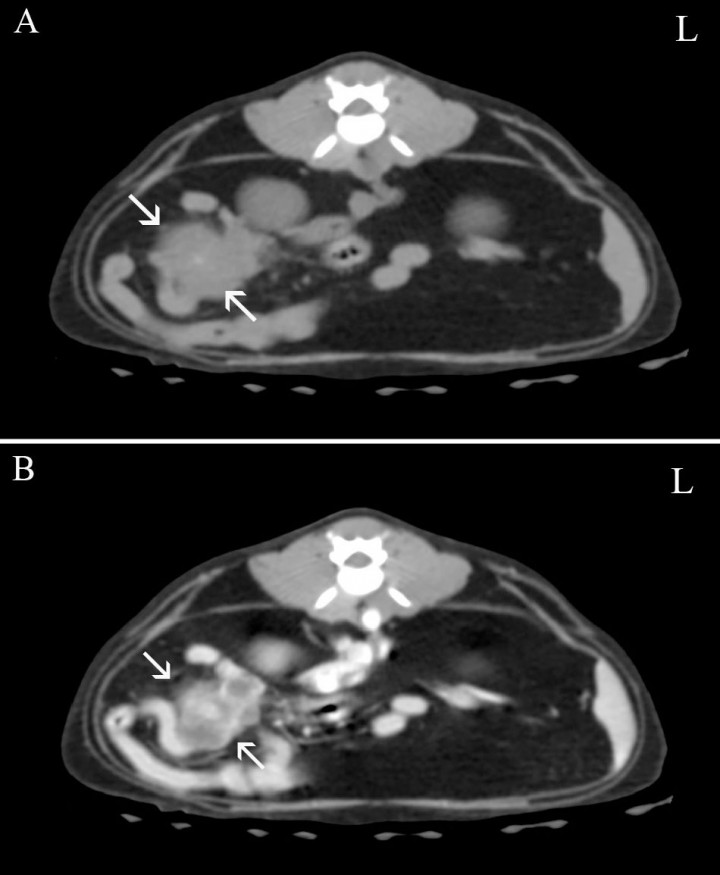

Se recomendó realizar una Tomografía Computarizada (TC) de abdomen (Fig. 4) para el estadiaje del tumor, en la que se visualizó una masa con origen en la válvula ileocecal, de morfología redondeada, homogénea, atenuación tejido blando (48 UH) y con un realce heterogéneo (50-150 UH) tras la administración del contraste. Dicha masa producía una disminución de la luz intestinal, observándose el íleon distendido con un diámetro de 3 cm en la zona más proximal a la masa (ratio diámetro del asa respecto a la altura L4 de 6, valor de referencia 1), y de 1,4 cm en la porción distal, con contenido heterogéneo. Los nódulos cólicos se visualizaron ligeramente aumentados de tamaño con un realce en anillo tras la administración del contraste.

<p>Imágenes de TC en plano transversal y ventana de tejido blando. (<strong>A</strong>) Precontraste. (<strong>B</strong>) Poscontraste. Se observa una masa con origen en la válvula ileocecal (flecha) que produce un realce heterogéneo tras la administración del contraste. L: izquierda.</p>

Imágenes de TC en plano transversal y ventana de tejido blando. (A) Precontraste. (B) Poscontraste. Se observa una masa con origen en la válvula ileocecal (flecha) que produce un realce heterogéneo tras la administración del contraste. L: izquierda.

Posteriormente, se realizó una TC de tórax donde no se observó ningún signo de metástasis.

Actualmente la TC es la técnica de imagen más recomendada para realizar el estadiaje de un tumor. Sin embargo, en este caso la TC no aportó ninguna información adicional a la obtenida en la ecografía. En ambas técnicas el diagnóstico más probable fue una neoplasia, y el diagnóstico definitivo obtenido mediante histopatología fue de un adenocarcinoma, no visualizándose signos de metástasis en el ganglio.

En conclusión, el signo de grava observado en las radiografías es compatible con una obstrucción intestinal parcial y crónica, siendo la neoplasia el diagnóstico más probable. En la TC, que en este caso no aportó ninguna información adicional a la obtenida en la ecografía, se observaron los signos más frecuentes de neoplasia como son pérdida de capas y engrosamiento de la pared.